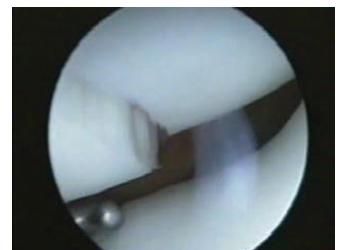

那么在外伤的过程当中,尤其是骨折的过程当中暴力一旦伤及到关节,很多人在x线上会明确的看到骨头的折断,但是在骨头上面尤其是涉及关节的骨头上面,软骨也会发生明显的撕裂。(下图就是典型的关节骨折软骨骨折的关节镜下所见)相信不用学医,也会看到骨折以后关节的软骨也会有明显的折断。